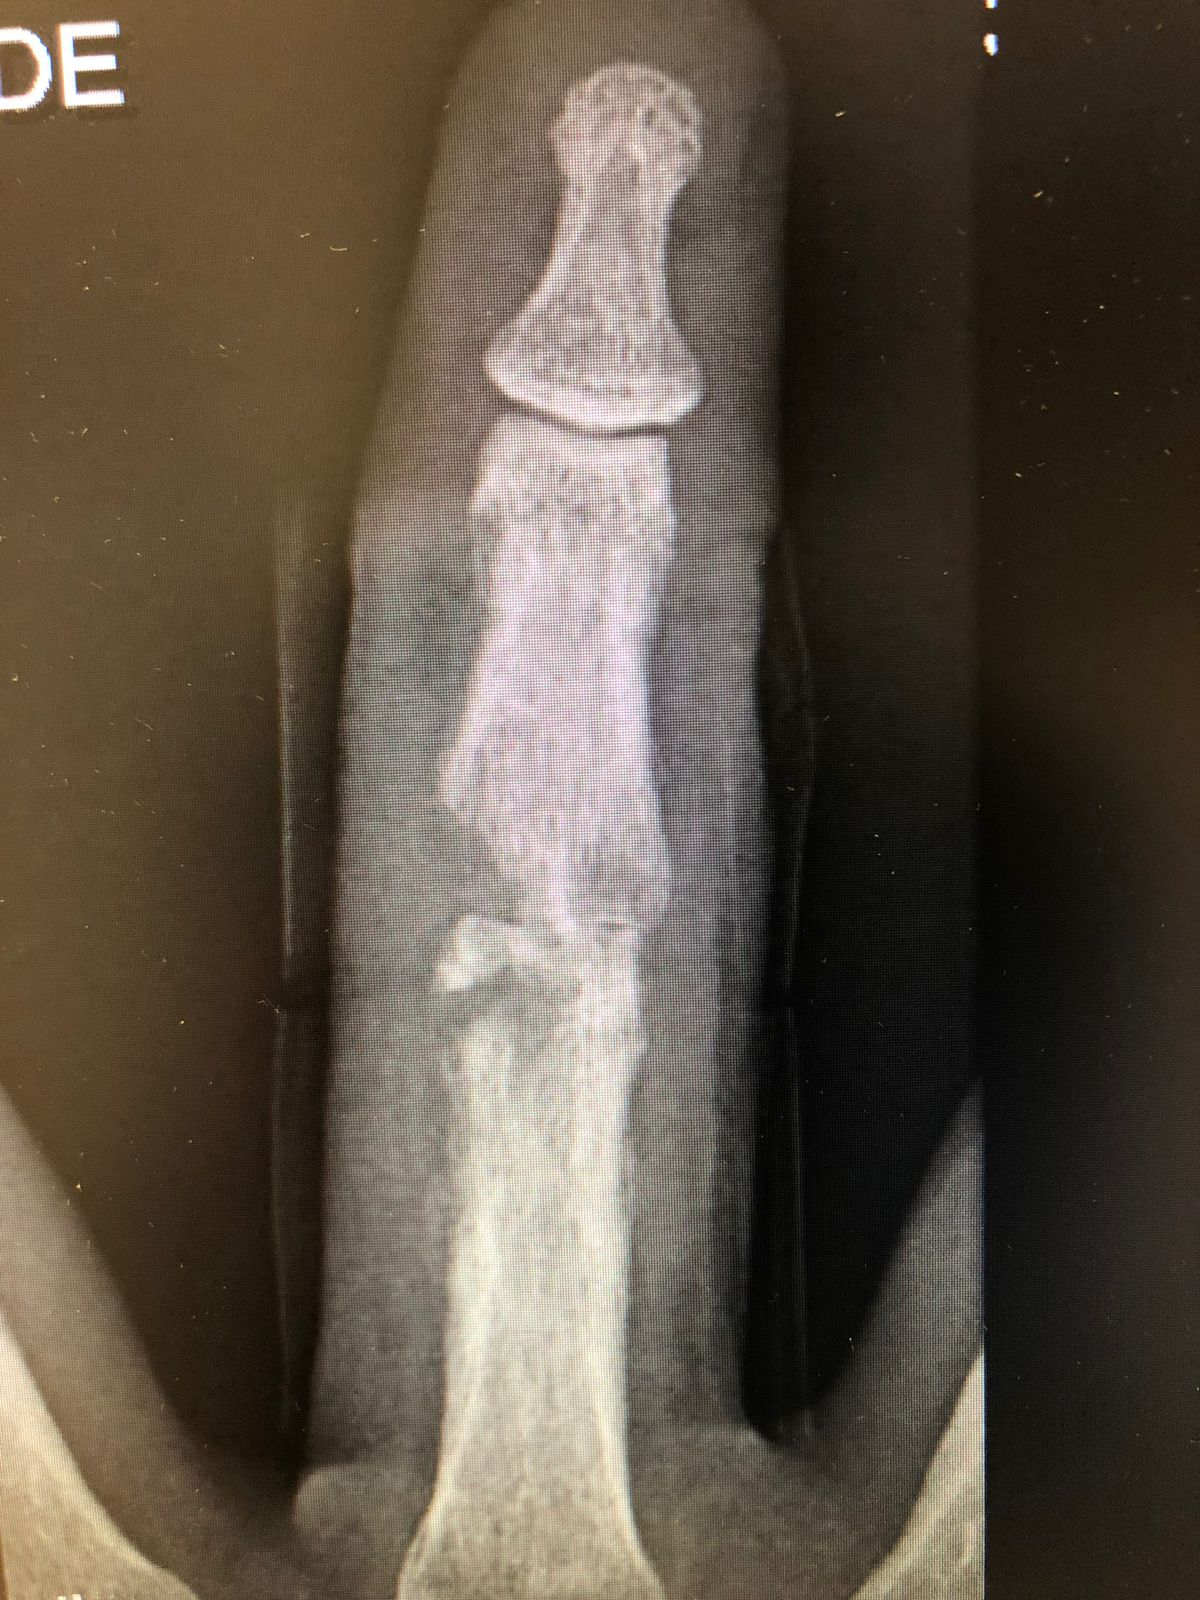

Tratamento especializado de fraturas, cortes profundos, lesões tendíneas, nervosas e amputações traumáticas da mão e membro superior, com foco na recuperação funcional e retorno seguro ao trabalho.

Utilização de técnicas cirúrgicas modernas, microcirurgia e acompanhamento funcional baseado em evidências científicas, proporcionando maior precisão e melhores resultados na recuperação.